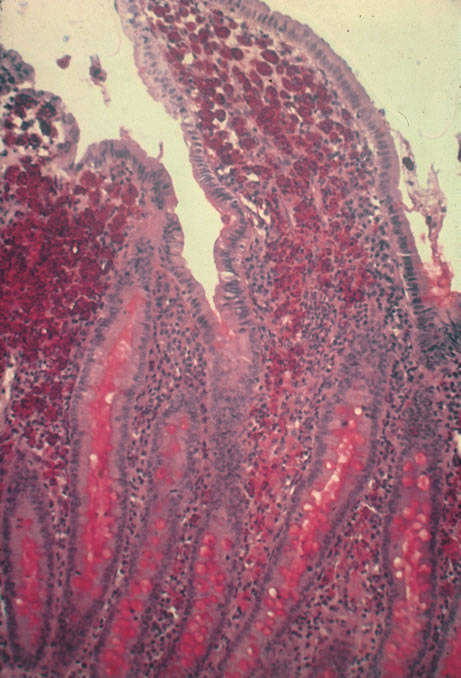

In primary ocular HSV infections, a severe follicular conjunctivitis with regional adenopathy is present. Vesicles may appear on the eyelid skin or lid margin, producing blepharitis (Fig. 3). Corneal involvement initially takes the form of a superficial punctate keratitis, which may progress to dendritic or geographic ulceration. Stromal infiltrates and uveitis are less common and relatively mild in primary disease. In uncomplicated cases, lesions usually heal completely in 2 to 3 weeks without scarring. Most cases of ocular HSV are recurrences. Recrudescent ocular herpes may take the form of dendritic or geographic ulcers, recurrent erosions, interstitial or disciform stromal keratitis, and anterior uveitis.3 HSV may also be an agent of retinitis and acute retinal necrosis (Fig. 4).